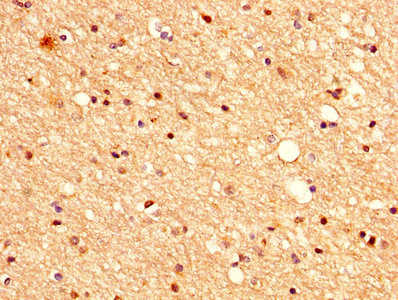

IHC image of CSB-PA745337HA01HU diluted at 1:500 and staining in paraffin-embedded human prostate cancer performed on a Leica BondTM system. After dewaxing and hydration, antigen retrieval was mediated by high pressure in a citrate buffer (pH 6.0). Section was blocked with 10% normal goat serum 30min at RT. Then primary antibody (1% BSA) was incubated at 4°C overnight. The primary is detected by a biotinylated secondary antibody and visualized using an HRP conjugated SP system.

IHC image of CSB-PA745337HA01HU diluted at 1:500 and staining in paraffin-embedded human brain tissue performed on a Leica BondTM system. After dewaxing and hydration, antigen retrieval was mediated by high pressure in a citrate buffer (pH 6.0). Section was blocked with 10% normal goat serum 30min at RT. Then primary antibody (1% BSA) was incubated at 4°C overnight. The primary is detected by a biotinylated secondary antibody and visualized using an HRP conjugated SP system.